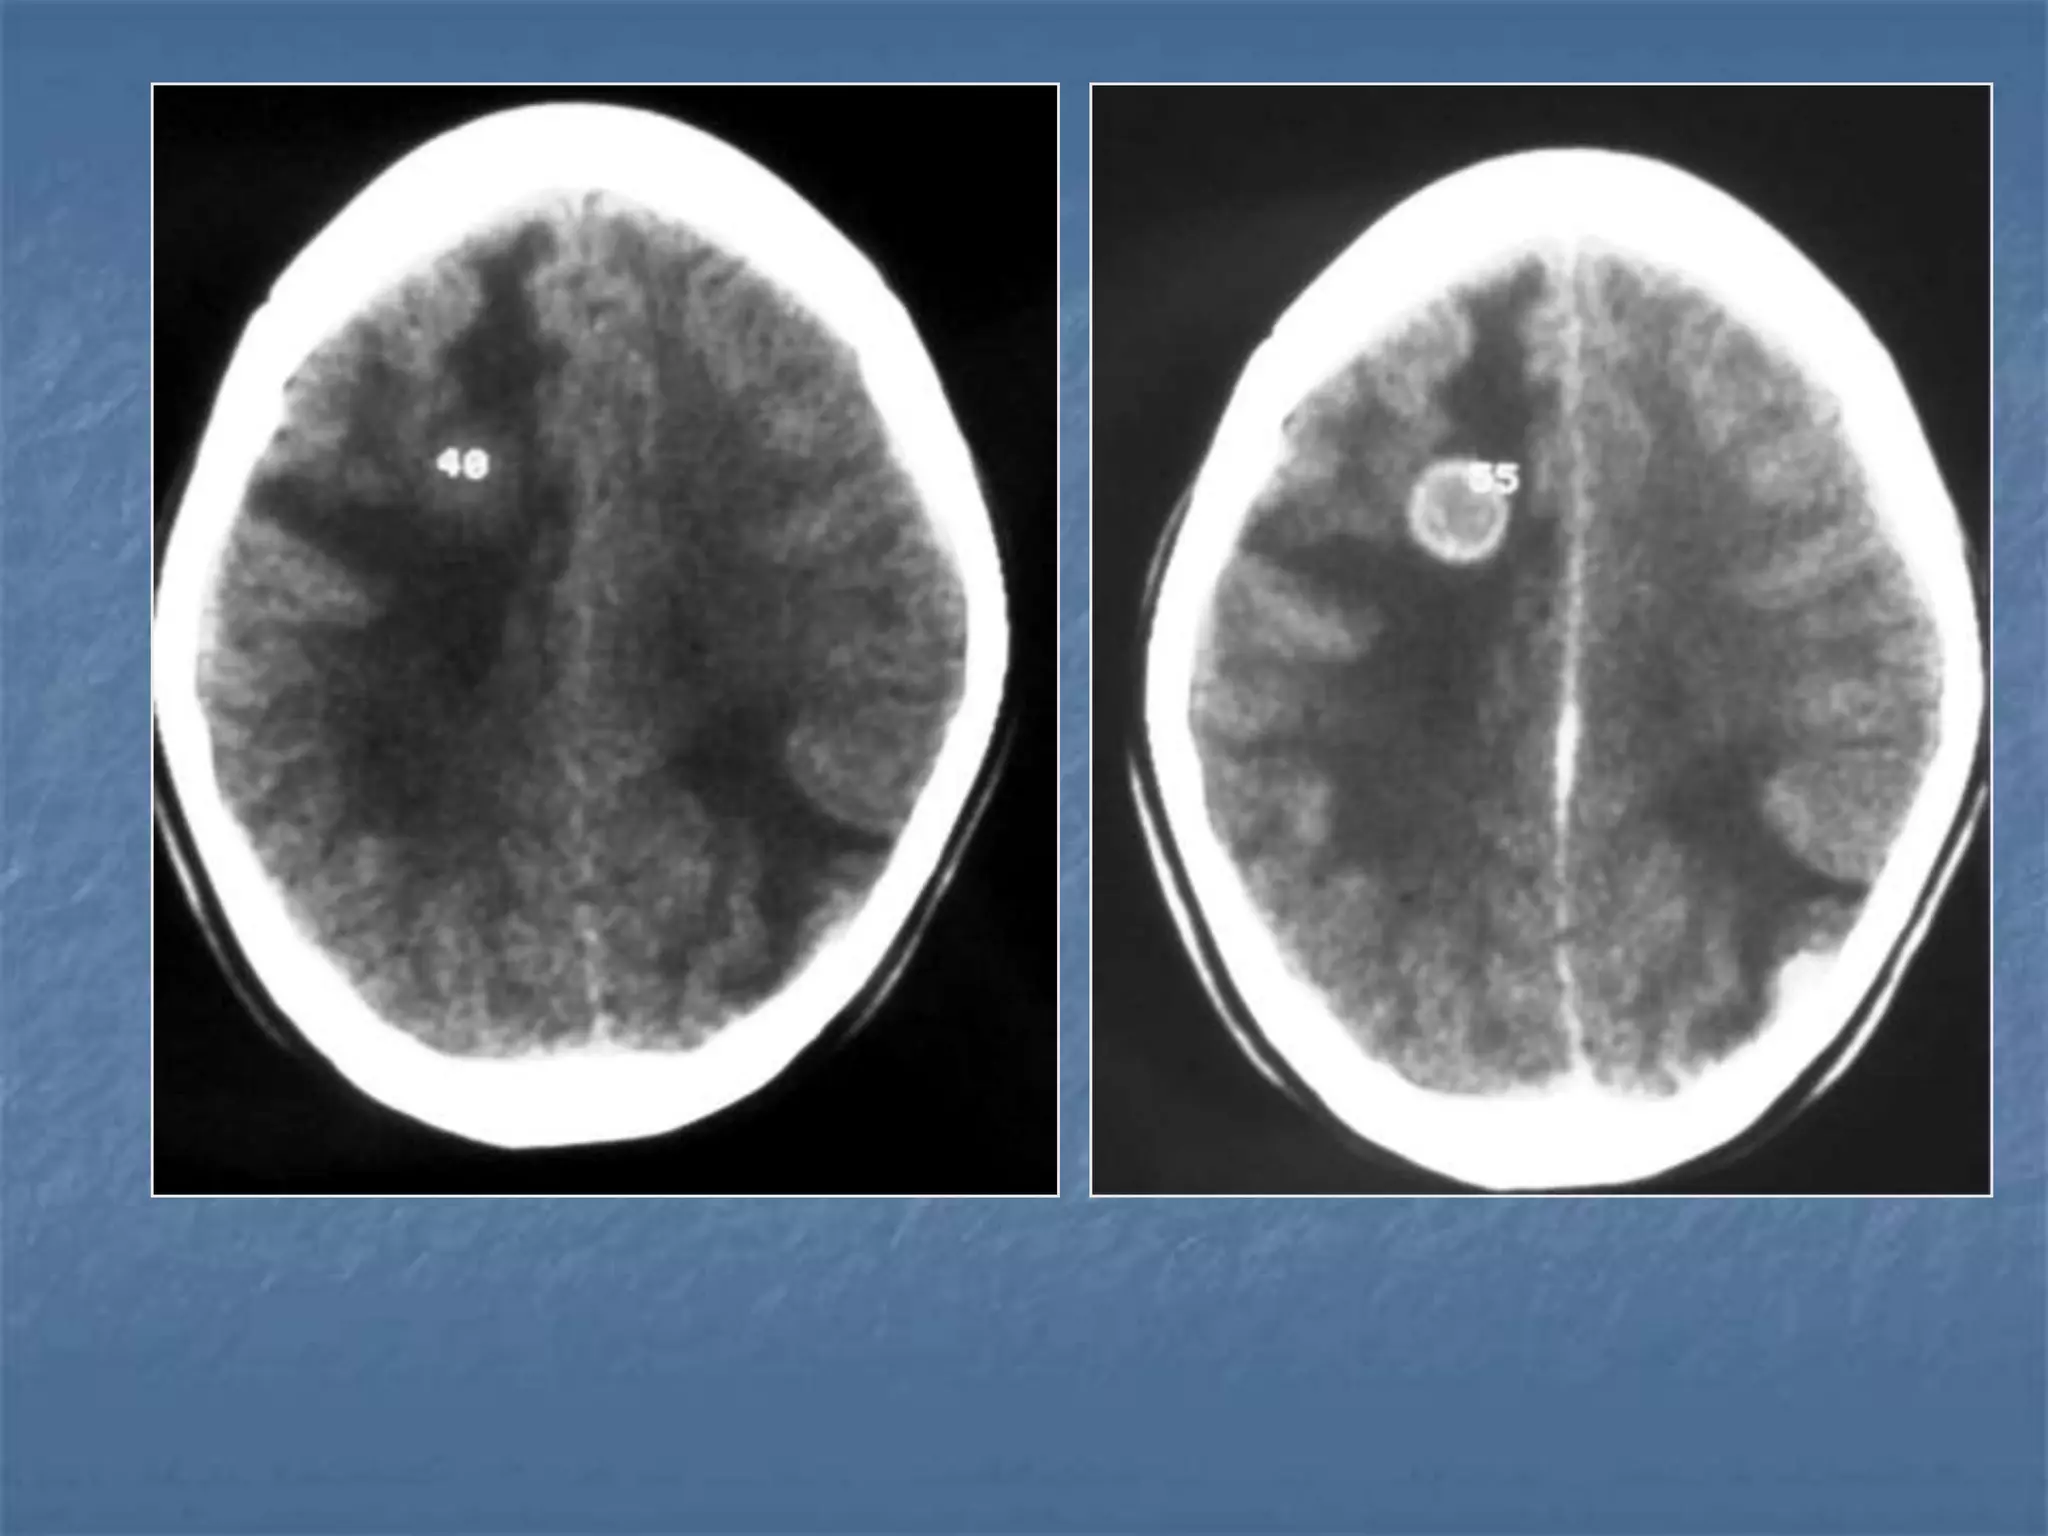

Hypertensive Hemorrhage

 Hypertensive hemorrhage accounts for

approximately 70-90% of non-traumatic primary

intracerebral hemorrhages. It is commonly due to

vasculopathy involving deep penetrating arteries

of the brain. Hypertensive hemorrhage has a

predilection for deep structures including the

thalamus, pons, cerebellum, and basal ganglia,

particularly the putamen and external capsule.

Thus, it often appears as a high-density

hemorrhage in the region of the basal ganglia.

Blood may extend into the ventricular system.

Intraventricular extension of the hematoma is

associated with a poor prognosis.